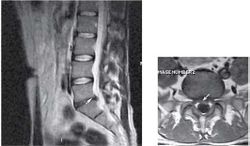

Пациентка С., 37лет, штукатур, заболела остро примерно 2 нед назад, когда утром после сна отметила острую боль при движении в шейном отделе позвоночника, ощущение скованности в шее, невозможность повернуть голову влево. В течение дня к болям в шейном отделе позвоночника постепенно присоединилась боль, иррадиирующая в левую лопатку, надплечье, по наружной поверхности левого плеча, которая имела жгучий и ломящий характер. Боль в руке и надплечье сохранялась в ночное время, нарушая сон, и частично уменьшалась в положении лежа с согнутой в локтевом суставе и заложенной за голову левой рукой. При наклоне головы в больную сторону пациентка эпизодически отмечала появление парестезий в виде «ползания мурашек» по наружной поверхности левого плеча. Прием НПВС и трамадола почти не приносил облегчения. В неврологическом статусе отмечено снижение болевой и температурной чувствительности в области левого надплечья и по наружной поверхности левого плеча, гипотония и снижение рефлекса с сухожилия двуглавой мышцы плеча слева, ограничение всех движений в шейном отделе позвоночника, но в большей степени - ротации и бокового сгибания влево. Наклон головы влево с аксиальным давлением на нее приводил к усилению боли в плече. Отмечено напряжение и умеренная болезненность при пальпации левой передней лестничной и трапециевидной мышц при отсутствии в них ТЗ. По данным рентгенографии шейного отдела позвоночника, выявлено снижение высоты межпозвоночных промежутков СIII-СIV СIV-СV, субхондральный остеосклероз, артроз дугоотростчатых суставов СIV-СV, унковертебральный неоартроз СIII-СIV СIV-СV Сагиттальный размер спинномозгового канала составил 16 мм. При МРТ шейного отдела позвоночника выявлена левосторонняя протрузия на уровне СIV-СV размером до 4,5 мм с компрессией дурального мешка, циркулярная протрузия на уровне СIII-СIV до 2 мм. Таким образом, при сопоставлении данных клинического обследования (невропатический характер болевого синдрома, наличие характерных для поражения корешка С5 чувствительных, двигательных и рефлекторных нарушений) с данными рентгенографии и МРТ позвоночника - наличие на соответствующем уровне (СIV-СV) латеральной протрузии и дистрофических изменений дугоотростчатого сустава с формированием сужения левого корешкового отверстия - у пациентки можно диагностировать компрессионную радикулопатию корешка СV слева, обусловленную левосторонней грыжей диска СIV-СV на фоне первично узкого спинномозгового канала на шейном уровне (Рис. 2). ЭМГ-обследование не проводили из-за небольшой (менее 3 нед) длительности заболевания и дальнейшей его положительной динамики на фоне лечения. Пациентке были назначены венотонические препараты (эскузан по 15 капель 3 раза в сутки), амитриптилин в дозе 50 мг/сут, внутривенные инфузии пентоксифиллина (5 мл 2% раствора), массаж мышц левой руки и надплечья, мануальная терапия (мобилизация шейных и грудных ПДС), ПИР трапециевидной и лестничной мышцы. На 10-е сутки лечения болевой синдром значительно уменьшился, его полный регресс произошел через 1,5 мес после начала заболевания.